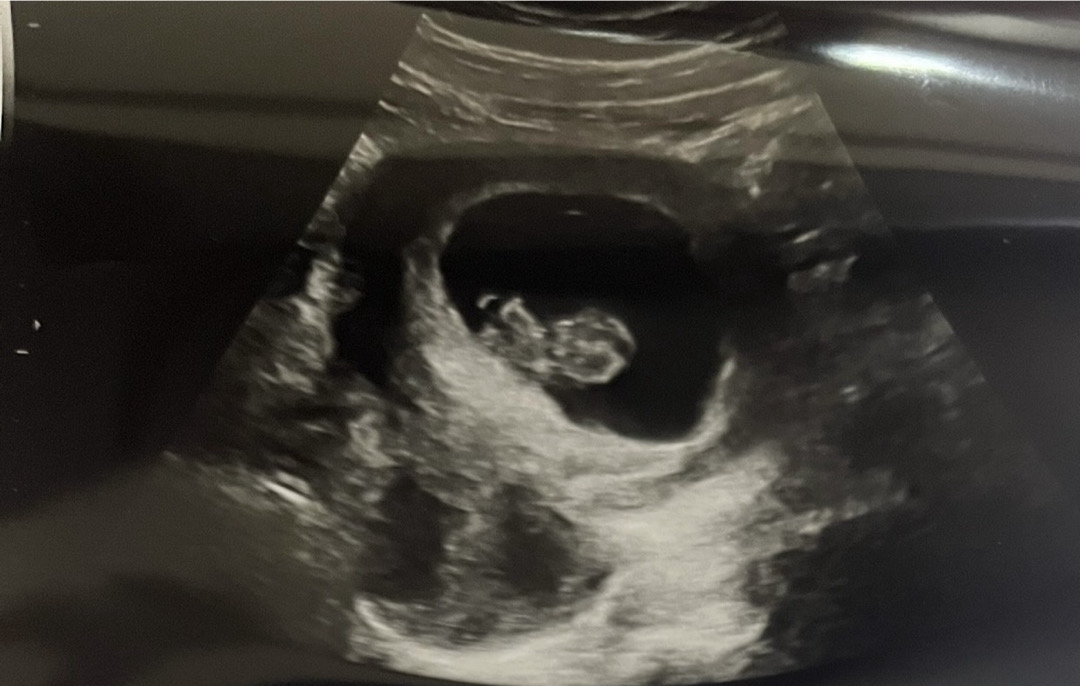

8주 5일차 움직이는 게 신기해요+먹덧

어제 병원가서 배 초음파 봤는데 머리랑 손발 구분도 되고 발 까딱거리면서 움직이는데 너무 귀엽더라구요ㅠㅠㅠ 요즘 일하느라 무리해서 잘 크고 있나 걱정했는데 다행히 잘 자라고 있는 것 같습니다 배에서 놀고 그런다고 하니까 신기하고 귀여워서 초음파 영상 계속 돌려보고 그래요ㅠㅠ 저는 5주차부터 입덧이 먹덧으로 와서 토하거나 그런 건 없지만 속이 비면 신물이랑 트름이 올라와서 이것도 이것 나름대로 힘드네요ㅠㅠ 땡기는 음식도 하나도 없고 고기는 금방 물리고 먹고 싶지도 않아요 ㅠㅋㅋㅋ먹덧인 분들은 저랑 증상 비슷하신가요? 1~2시간 꼴로 배도 금방 꺼져서 큰일이에요ㅠㅠ

와 젤리곰 너무 귀여워요ㅠㅠ 6주차 지금 3mm라는데 2주만에도 금방금방 크네요 ㅎㅎ

그쵸 생각보다 쑥쑥 자라더라구요~2주 뒤면 젤리곰을 보실 수 있을 거예요~~진짜 너무 신기하고 귀여워요 ㅋㅋㅋ